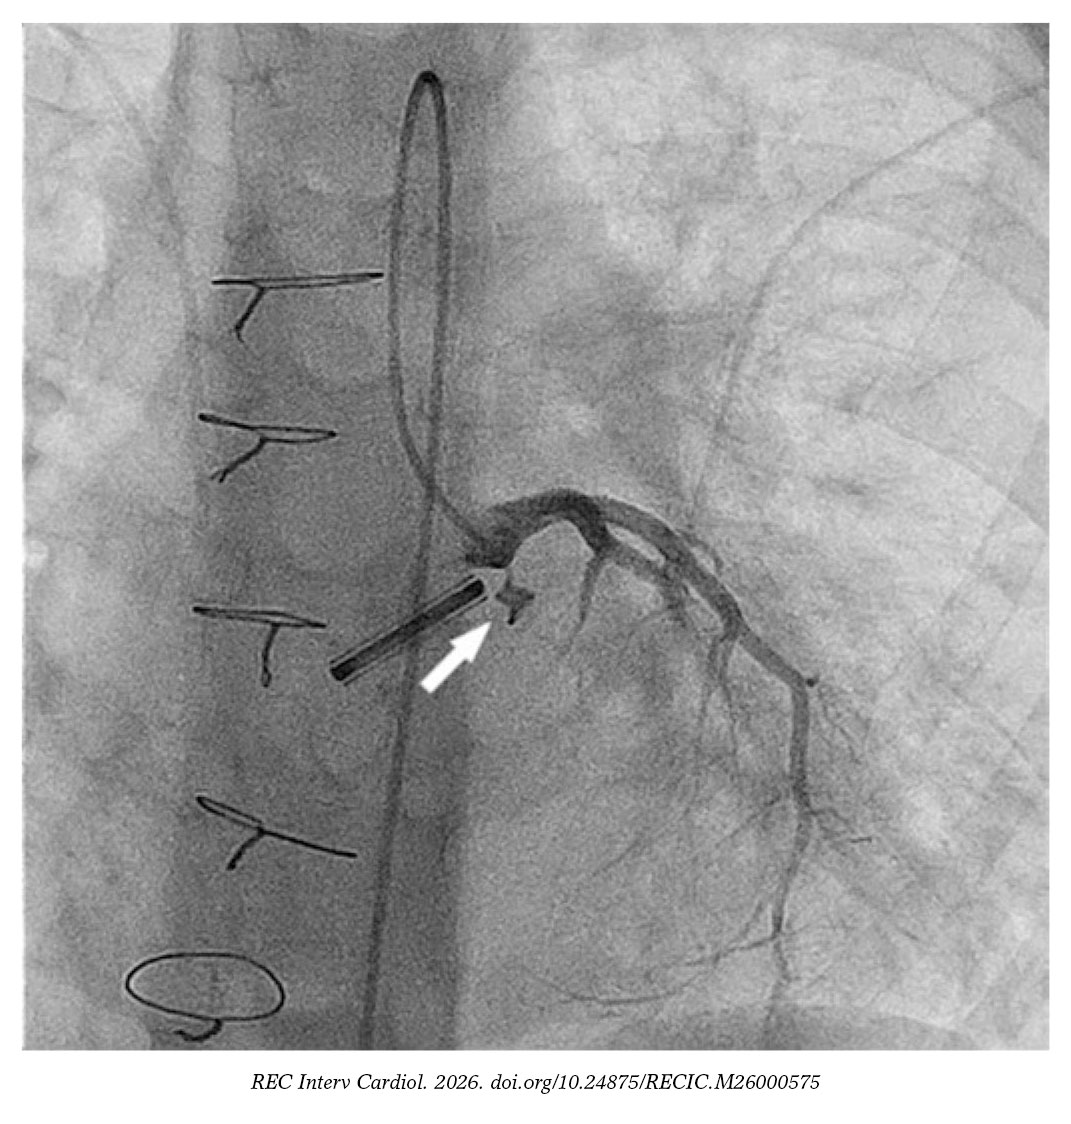

Se sondó la fístula con un catéter NIH 4F modificado (Cordis, Estados Unidos) y una guía hidrófila de 0,035 pulgadas sobre la que se avanzó un catéter de liberación de 4Fr para implantar un dispositivo Nit-Occlud PDA 4 × 4 mm (PFM Medical, Alemania) (figura 2 y vídeo S2). Se eligió este dispositivo en lugar de oclusores de malla de nitinol porque se consideró que la longitud de estos últimos era excesiva y que sus discos de retención podían interferir con la coronaria.

Figura 2.